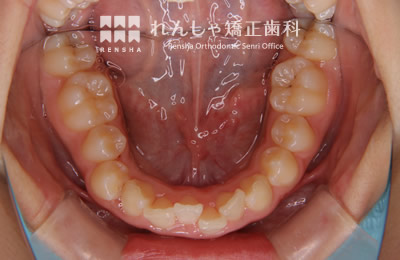

中高生

永久歯列はほぼ完成してしますが、歯列を側方だけでなく後方へも拡大し、埋まっていた右上奥歯を引っ張り出しています。

治療前

治療中

治療後

| 主訴 | 埋まったままでてこない歯がある |

|---|---|

| 診断名 | Angle Class II 小臼歯の埋伏と叢生を伴う上顎前突 |

| 初診時年齢 | 13歳5か月 |

| 装置名 | マルチブラケット装置 |

| 抜歯非抜歯 | 非抜歯 |

| 治療期間 | 2年3か月 |

| 費用の目安 | 約82万円+消費税(検査料金、都度の処置費用等も合わせた総額) |

| リスク副作用 | 歯の移動に伴う軽微な歯根吸収、歯槽骨吸収、歯肉退縮(本症例では軽度の歯根吸収を認めた)、矯正器具装着中のカリエスリスク増大(本症例ではカリエス発生無し) |